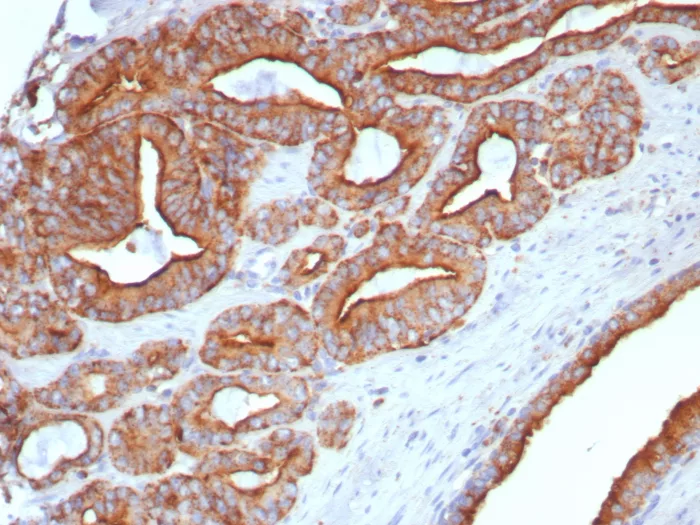

Lysosome-associated membrane proteins (LAMP) are glycosylated type I membrane proteins that play a role in the biogenesis of the pigment melanin. LAMP-1 (also designated CD107a) and LAMP-2 (also designated CD107b) are involved in a variety of functions, including cellular adhesion, and are thought to participate in the process of tumor invasion and metastasis. Newly synthesized LAMP-1 and LAMP-2 proteins are sorted at the trans-Golgi network and are transported intracellularly via a pathway that is distinct from the Clathrincoated vesicles used for the mannose-6 phosphate receptor. LAMP-1 is expressed on the surface of Thrombin-activated but not resting platelets, and it is thought to be involved in the adhesive, prothrombic properties of these cells. Both LAMP-1 and LAMP-2 are involved in maintaining lysosome acidity and protecting the lysosomal membranes from autodigestion, and their expression is increased in patients with lysosomal storage disorders.